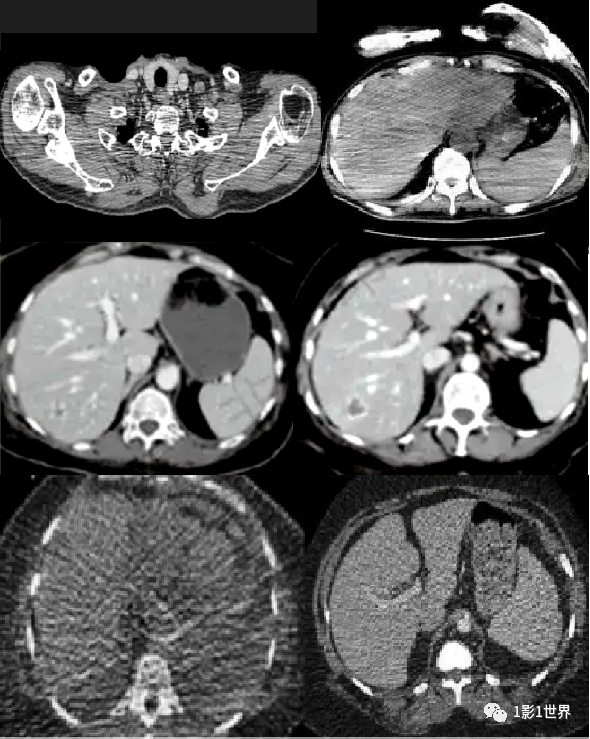

类似硬膜下血肿的运动伪影

左下肺运动伪影,因呼吸控制不好,而出现的类似支气管扩张

的运动伪影